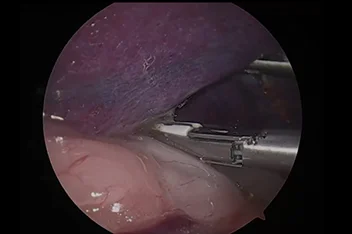

관절경

개,고양이 들은 다양한 관절질환이 존재하고, 복합적으로 존재하는 경우도 빈번합니다.

정확한 진단이 나지 않은 뒤 수술을 하게되면 증상개선이 더디거나 개선이 안될 수 있어, 정확한 진단이 필요합니다.

관절의 경우 X-ray 촬영등으로 진단의 한계가 명확하며, 상위 검사인 CT, MRI 촬영으로도 진단의 한계가 있습니다.

이때 관절경은 내부 구조물들을 직접 시각화 하여 보다 정확한 관절의 상태를 확인하고 진단할 수 있으며, 진단과 치료를 동시에 진행하는 경우도 있습니다. 대표적으로 십자인대단열(CCLR), 골연골염(OCD), 자뼈꿈치돌치유합부전(UAP), 내측관상돌기질환(MCD) 등에 활용될 수있습니다.

관절경 팔꿈치관절(Elbow) 확인

관절경 무릎관절(Stifle) 확인 (반월판 및 십자인대)

* 리본동물의료센터 케이스 사진으로 무단 복제 및 도용을 금지합니다.